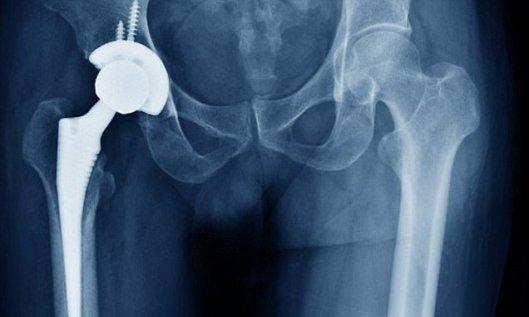

Doctors are being urged to check for signs of dementia or heart disease in hip implant patients.

There are concerns that the metal-on-metal devices are leaching toxic chemicals into the blood which cause serious health complications.

The Medicines and Healthcare products Regulatory Agency announced last month that patients would be called in for x-rays and blood tests to check for adverse reactions.